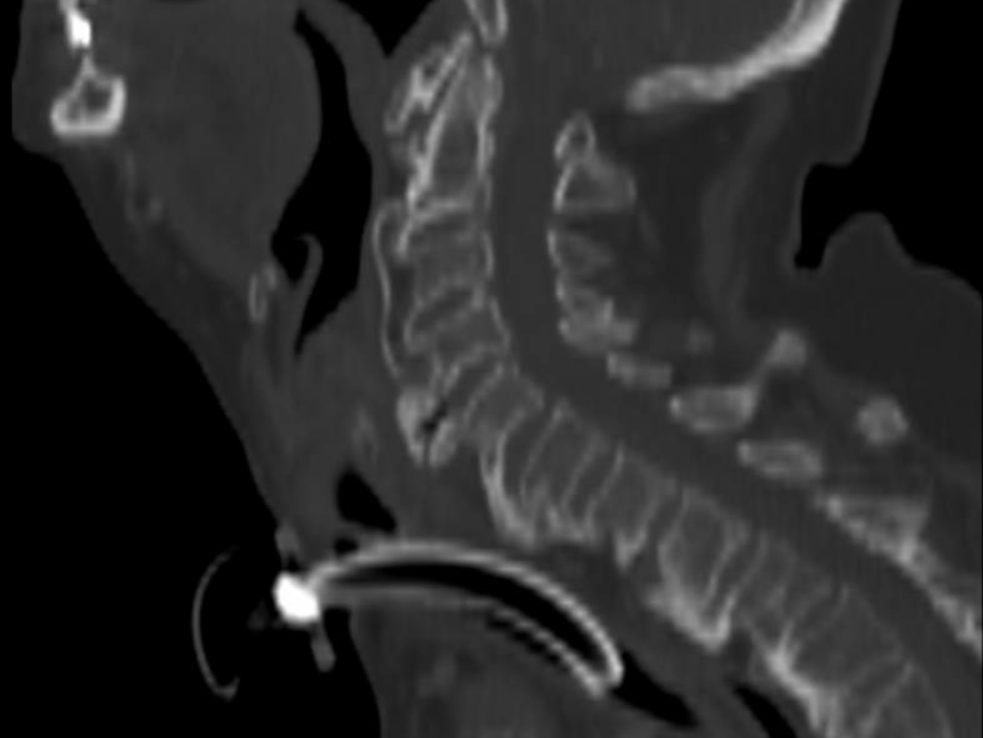

Case Presentation: An 89-year-old woman presented to the emergency department with dyspnea and dysphagia. She gave a one-year history of progressive hoarseness of voice, intermittent dyspnea, and dysphagia. Physical exam was positive for stridor, but negative for any neurological, thyroid, or pulmonary disease. Initial management involved administration of dexamethasone and urgent transnasal flexible fiberoptic laryngoscopy, which showed bilateral vocal fold palsy. An emergency tracheostomy was performed. Neck soft tissue radiography and brain MRI were unremarkable. CT of the soft tissues of the neck with contrast showed diffuse edema of the hypopharynx and bulky anterior cervical osteophytes. Chest CT showed findings of DISH in the thoracic spine, with no evidence of compression of the recurrent laryngeal nerves. A modified barium swallow showed aspiration and she underwent gastric tube placement. Definitive treatment with anterior cervical vertebrectomy and osteophyte removal of C4, C5, and C6 was performed with remarkable improvement. After a period of rehabilitation, both the feeding tube and the tracheostomy were successfully removed.

Conclusions: Giant osteophytes causing direct pressure on the hypopharynx and vocal cords or pressure on the recurrent laryngeal nerves should be kept in mind during evaluation of elderly patients with dysphagia, stridor, and dysphonia.